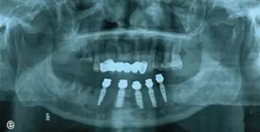

種植后修復(fù)

戴上套筒冠基臺進行即刻修復(fù)。注意不是所有植入的種植體都可以進行即刻修復(fù),醫(yī)師可以通過扭力值并結(jié)合ISQ松動度測量值來選擇修復(fù)的種植體。

圖18 進行即刻修復(fù):a.戴上基臺;b.在基臺上戴入套筒冠;c. 套筒冠固位到原有義齒上;d.患者戴上有套筒冠的覆蓋義齒;e. 即刻修復(fù)完成后曲面體層片